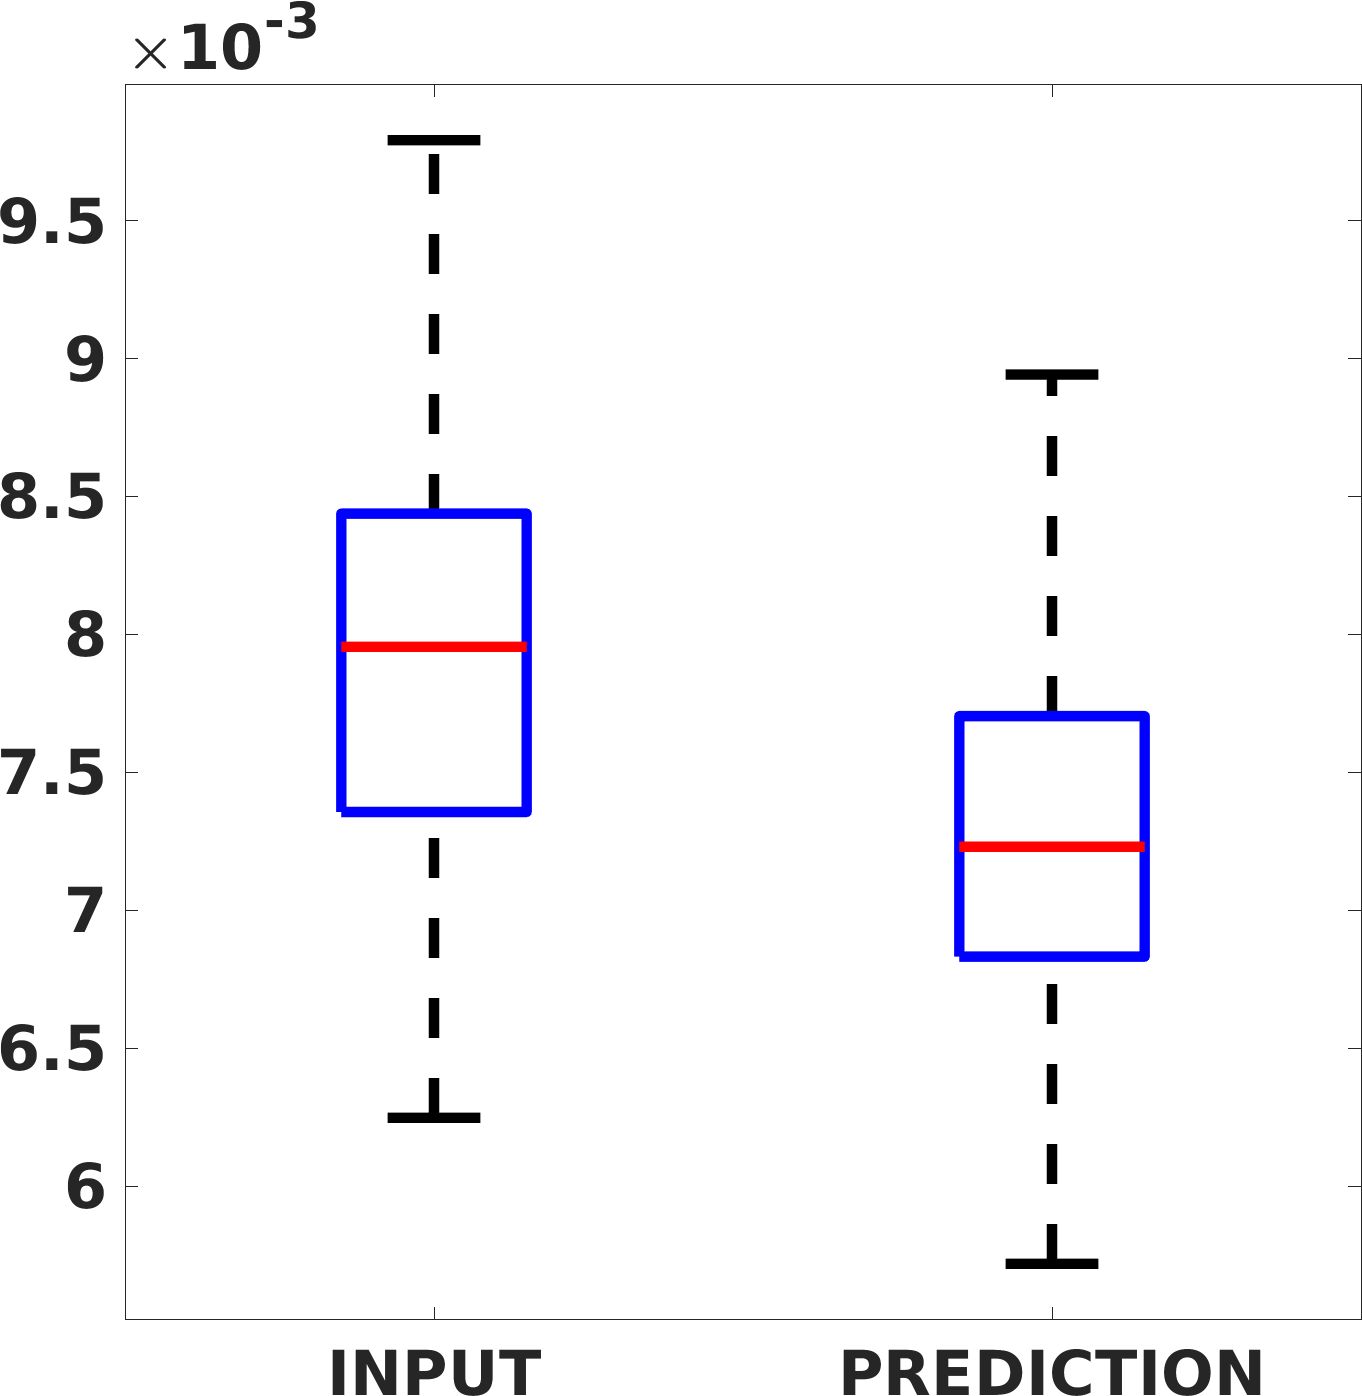

Fig. 8 shows the box plot of the SSIM (a-b-c, left) and MAE (a-b-c, right) quantitative metrics, as performed for PSNR metric. Also, these metrics show that our method improves the results of Cubic convolution both in terms of average value and variability. For example, the SSIM median value improves of on obstetric 4X images and the MAE median value improves of on cardiac 2X images.

Fig. 17 (right) shows the histogram of the absolute value of the error with respect to the target, of the prediction and Cubic convolution respectively. This result shows that our framework increase of and (2X and 4X, respectively) the number of pixels where the prediction error is lower than 5, which is very similar to the target when visually analysing the images, and improved with respect to the learning framework applied to raw images. According to Fig. 18, our method improves the accuracy of Cubic convolution. For example, the SSIM increases of on cardiac 2X and the MAE increases of on abdominal 4X.